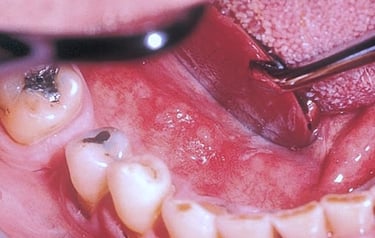

Oral Lesions

Thorough assessment and compassionate care for chronic or recurring oral ulcers, with treatment plans focused on addressing the underlying cause.